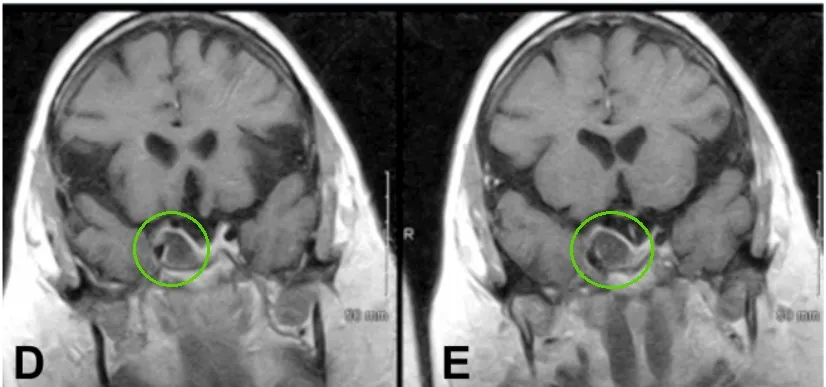

进行放疗一年后,她的右眼眼皮无法控制地耷拉下来,看东西出现重影,眼球转动困难——这是典型的动眼神经麻,MRI检查发现她的右侧海绵窦内肿瘤复发了,而且正在进展。

术前肿瘤持续生长进入海绵窦

INC福教授为艾拉采用标准经鼻经蝶窦入路内镜手术,随后通过移除海绵窦颈内动脉前段上的骨质进行外侧扩展术野。

术后,艾拉动眼神经麻症状得到缓解,恢复过程平稳。患者维持术前药物治疗方案。病理学检查确认病变为垂体腺瘤,未见恶变特征。

经过三年随访,影像学检查未发现肿瘤复发或生长。她的人生轨道,在经过一段惊心动魄的颠簸后,终于又回归了宁静与光明。